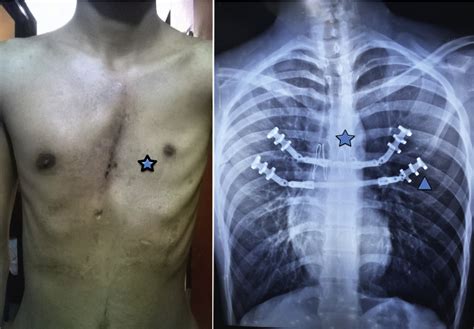

Modified Ravitch Procedure for Left Poland Syndrome Combined With

Source: www.annalsthoracicsurgery.org

A 25-year-old man had recurrent pectus excavatum after a Nuss procedure

Source: www.researchgate.net